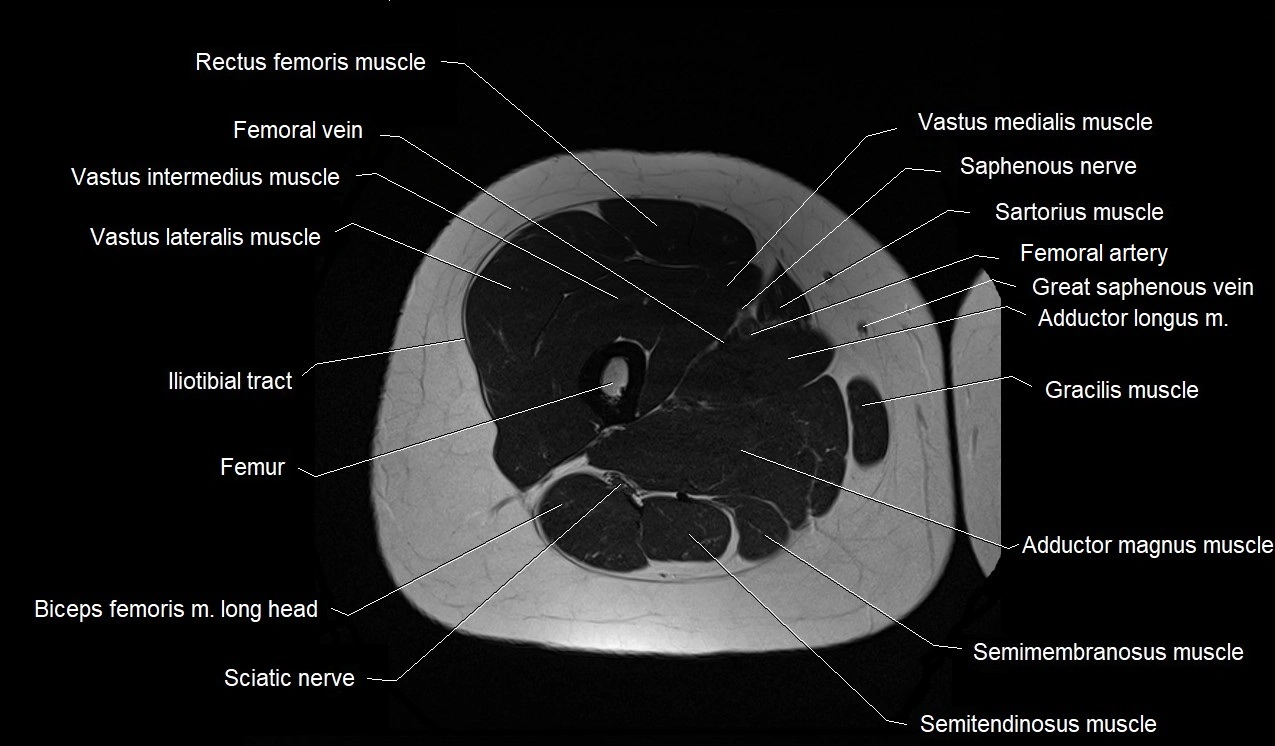

- Biceps femoris muscle (Long head)

- Femoral artery

- Femoral vein

- Femur

- Gluteus maximus muscle

- Gracilis muscle

- Iliotibial tract

- Rectus femoris muscle

- Saphenous nerve

- Sartorius muscle

- Semimembranosus muscle

- Semitendinosus muscle

- Vastus intermedius muscle

- Vastus lateralis muscle

- Vastus medialis muscle